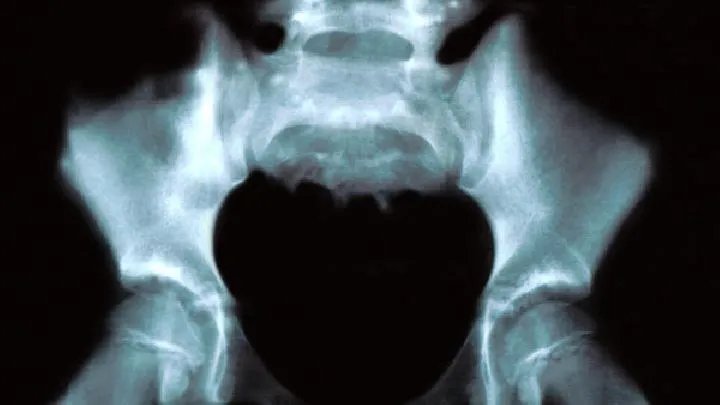

1.腰椎间盘突出症:腰椎间盘突出症是引起坐骨神经痛的最常见原因。由于髓核突出或脱出,纤维环破裂,压迫或刺激相邻的脊神经根,从而产生坐骨神经痛的症状。2.腰骶神经根炎:因感染、中毒、营养代谢障碍或劳损,受寒等因素发病,也是常见的引起坐骨神经痛的原因。一般起病较急,且受损范围常常超出坐骨神经支配区域,表现为整个下肢无力、疼痛、轻度肌肉萎缩、除跟腱反射外,膝腱反射也常减弱或消失。